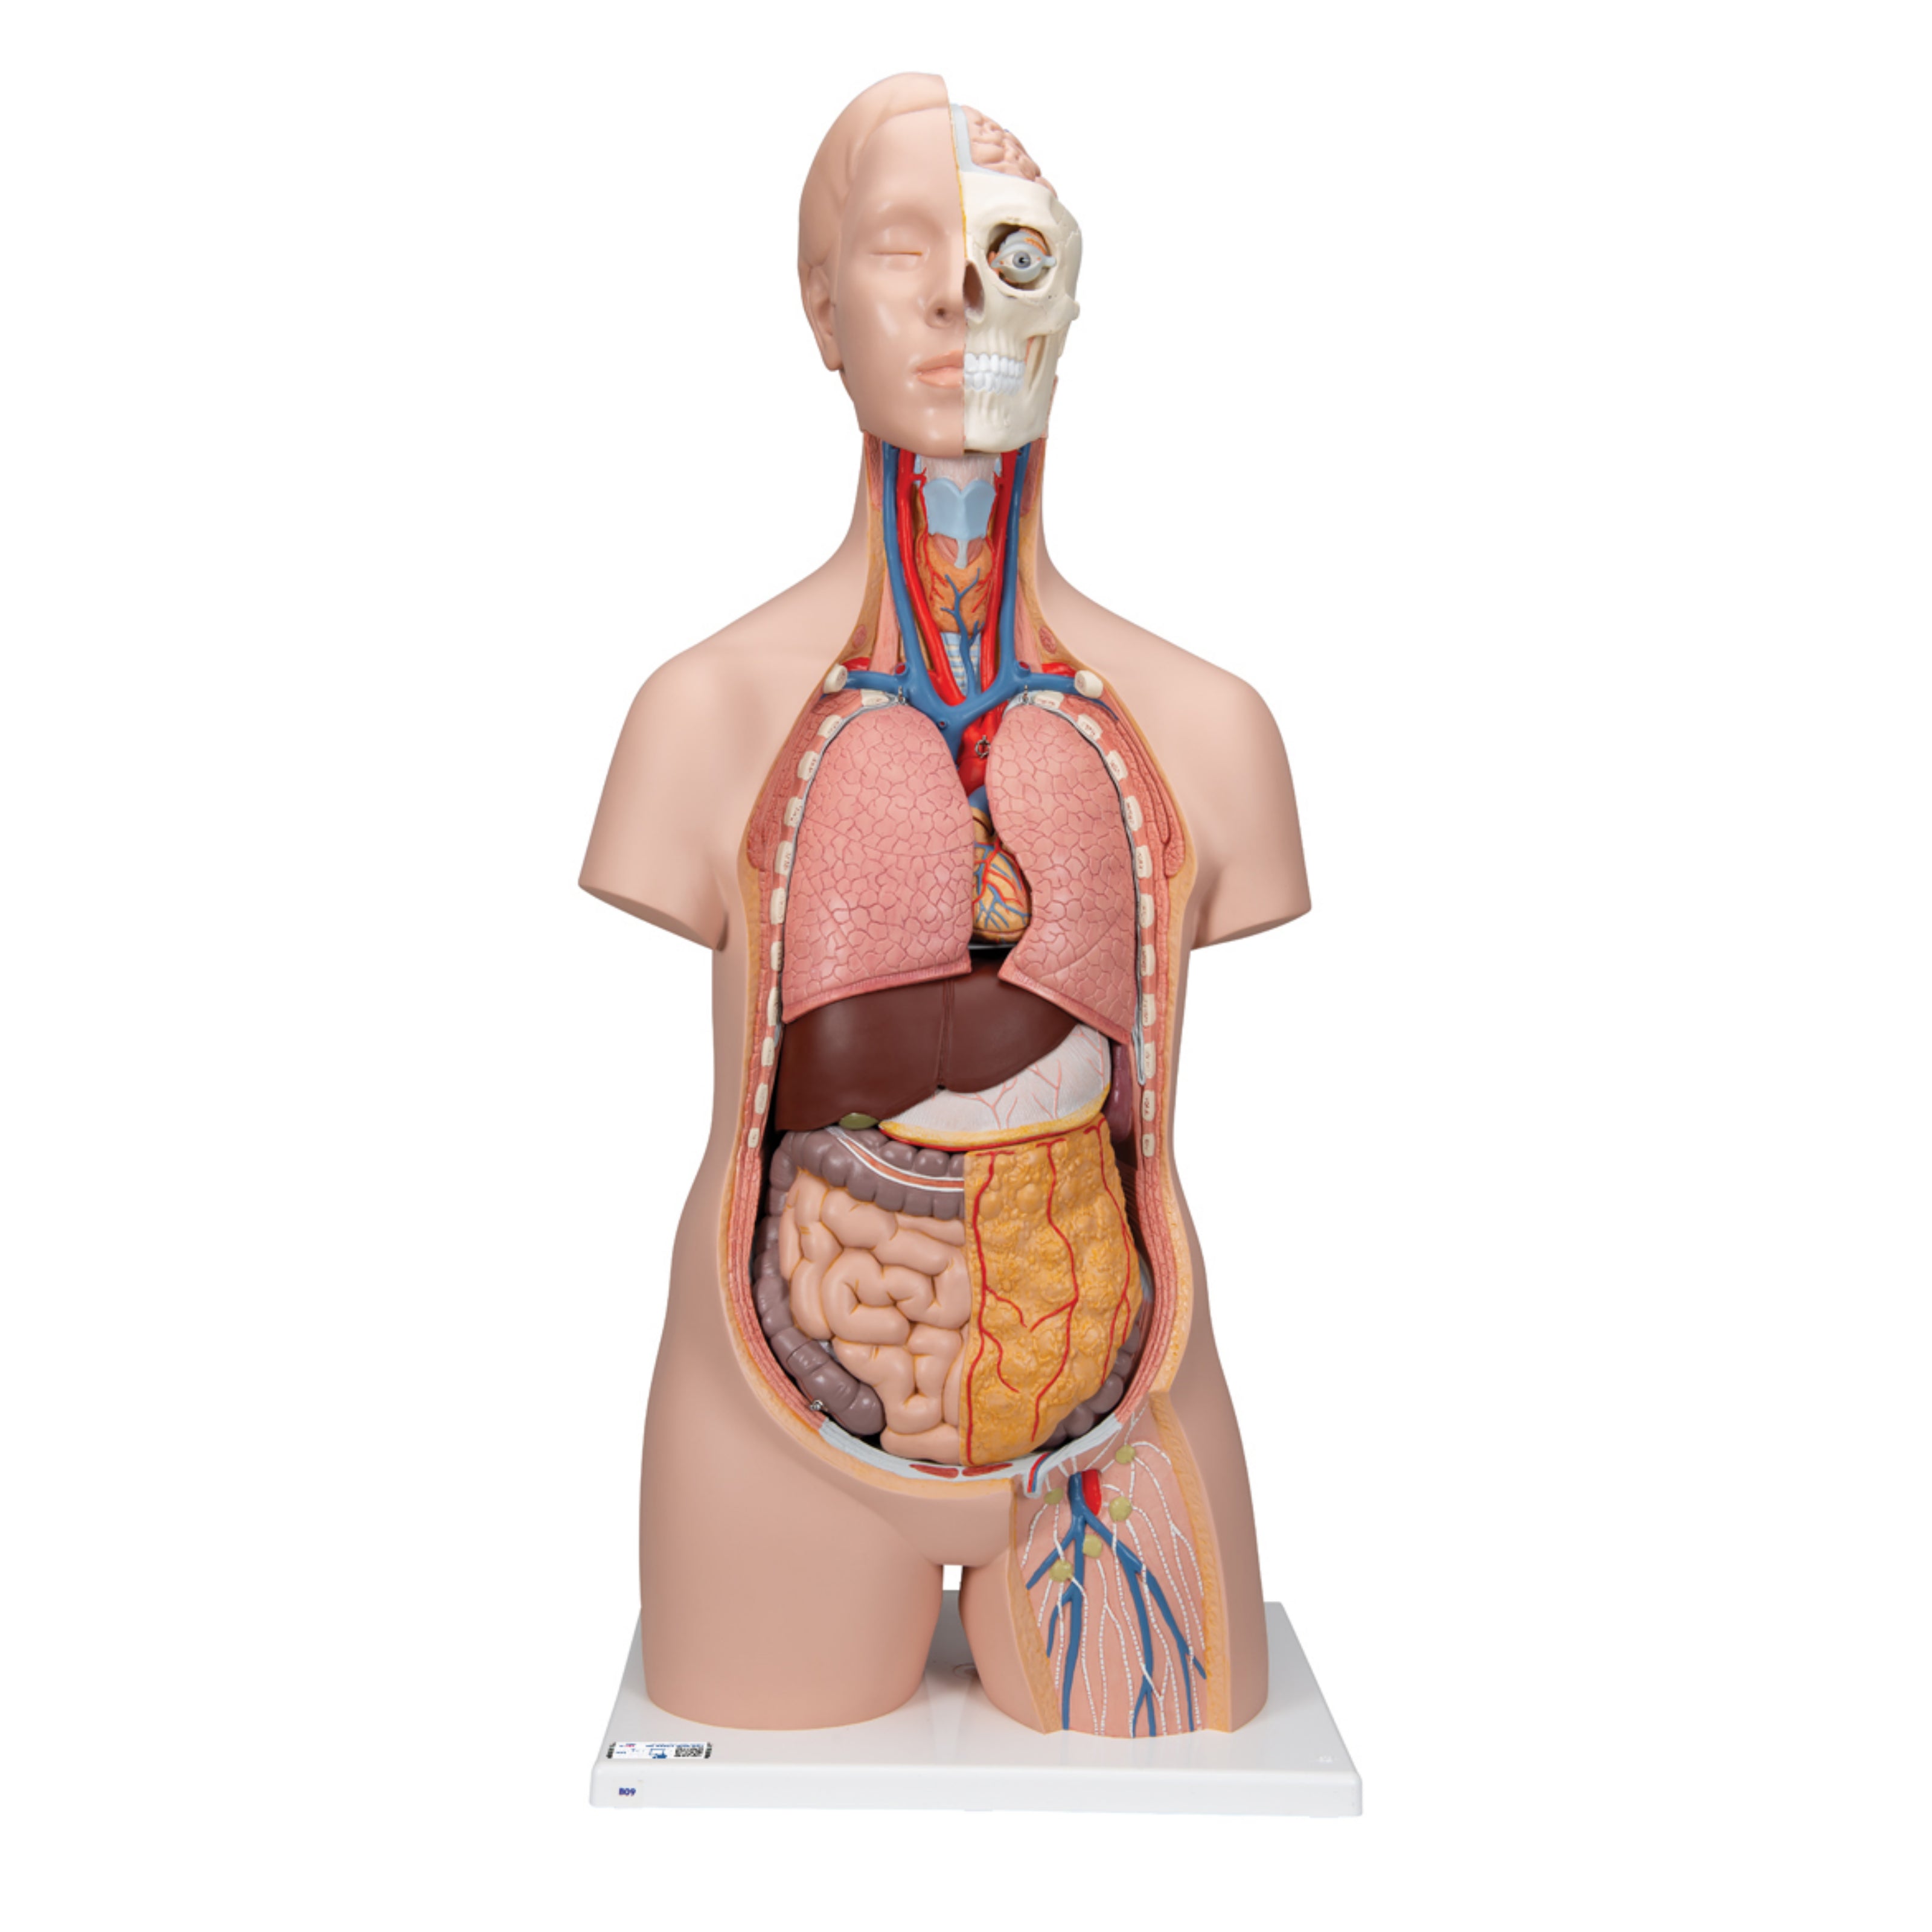

Torso clásico con espalda abierta, 18 partes - 3B Smart Anatomy

Precio de venta$33,762.96